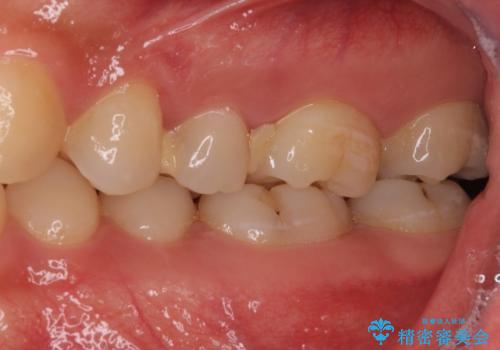

左上奥と右下奥に治療中の歯があり、虫歯を取っている途中で仮詰めの材料が充填されている状態でした。

仮詰め材を外すと虫歯が残っていたので、全てを取り除いた後に、ゴールドインレーの型どりを行いました。

ゴールドインレーをご自身で選択いただいたものの、どういった仕上がりとなるか不安を感じていたようですが、実際に装着された口腔内をご覧になり、思ったほど金属色が気にならないとのことでした。